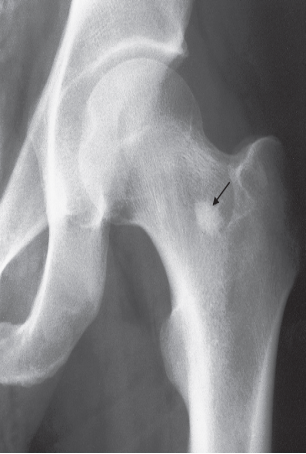

increase in bone density

May also be focal or generalized; e.g. Sclerosis

X-ray of Musculoskeletal System